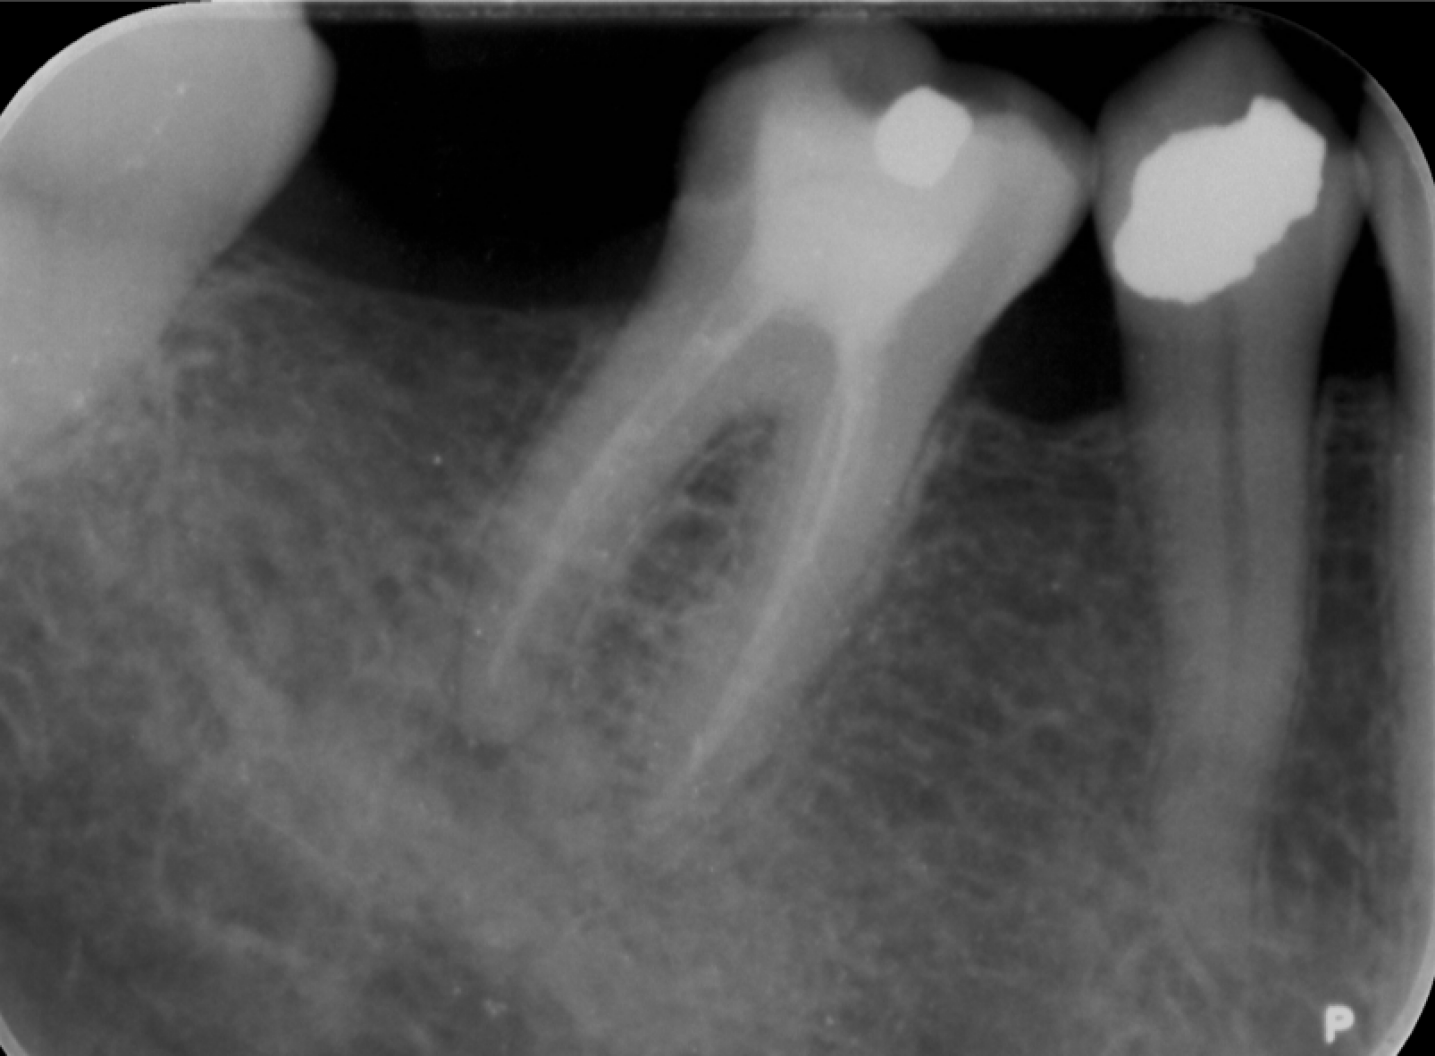

Fig. 2: (a) - (d) Dental disease detection results. (e) The reference ground truth (GT).

Comparative Results: As shown in Table 1, DentalX achieves 45.9 AP.5 and 21.0 AP.5:.95, outperforming other baseline detectors in disease detection. It surpasses YOLOX by 5.2 AP.5, while incurring only a slight drop in the inference frame per second (FPS) (6% less than YOLOX). Due to the large number of parameters, DINOv3 fails to generalize well to our small dental dataset, achieving only 30.1 AP.5. Moreover, our method significantly outperforms the Faster R-CNN model, a commonly used object detector for disease detection in previous studies [Chen2021caries_bl, zhu2022caries, Lee2022caries_pano, Liu2022marginalbl, ba2023perilesion_pano] by 11.7 AP.5. Fig. 2 visualizes the disease detection result of the object detectors. DentalX is consistently accurate with fewer false positives, further validating its capability to constrain the detected dental disease based on the structural context.